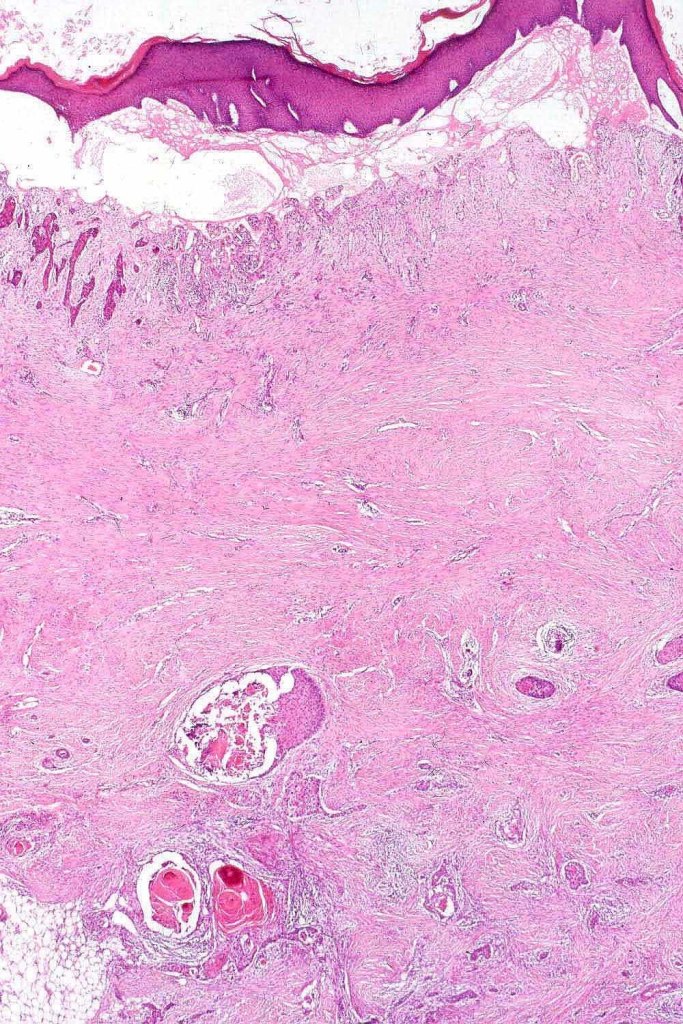

Histological features

•Generally, tumors are well differentiated although they can later develop a more poorly differentiated morphology

•Keratoses may represent a precursor & sometimes histological distinction between very marked epidermal hyperplasia (pseudoepitheliomatous) and early SCC can be problematical (personal observation)